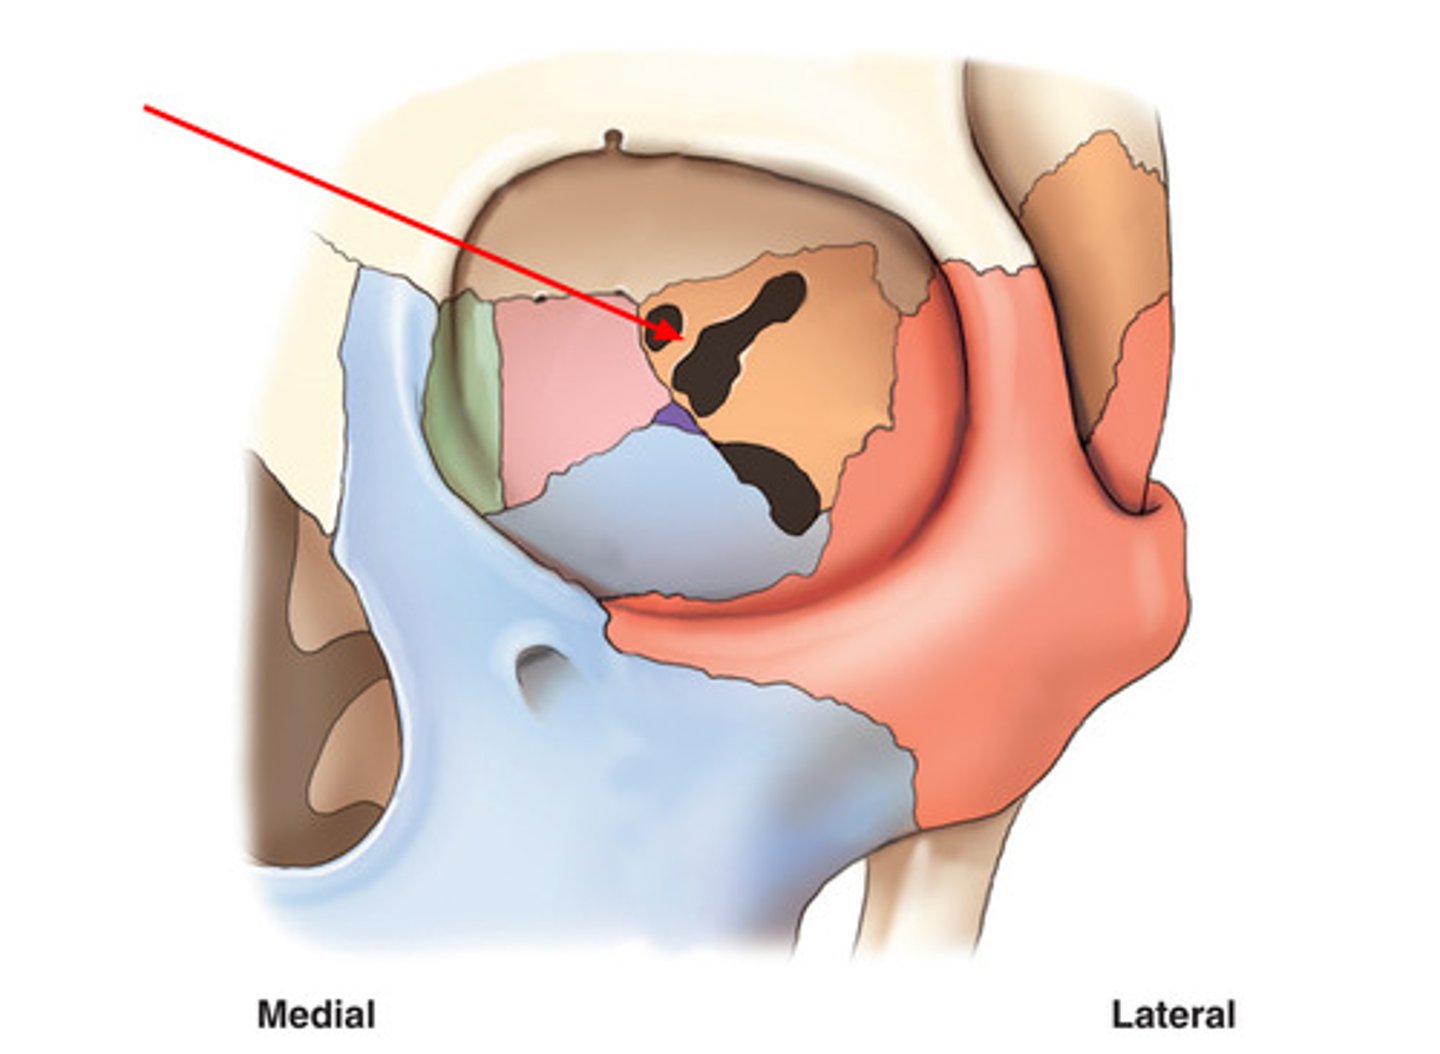

optic foramen in orbit

sphenoid strut